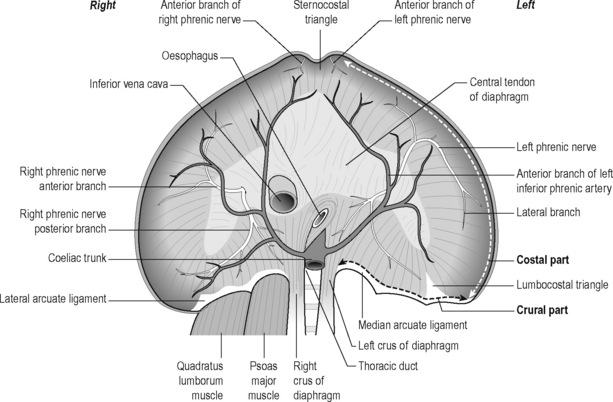

Анатомия диафрагмы и треугольника Бохдалека

Раздел: Визуальный дайджест